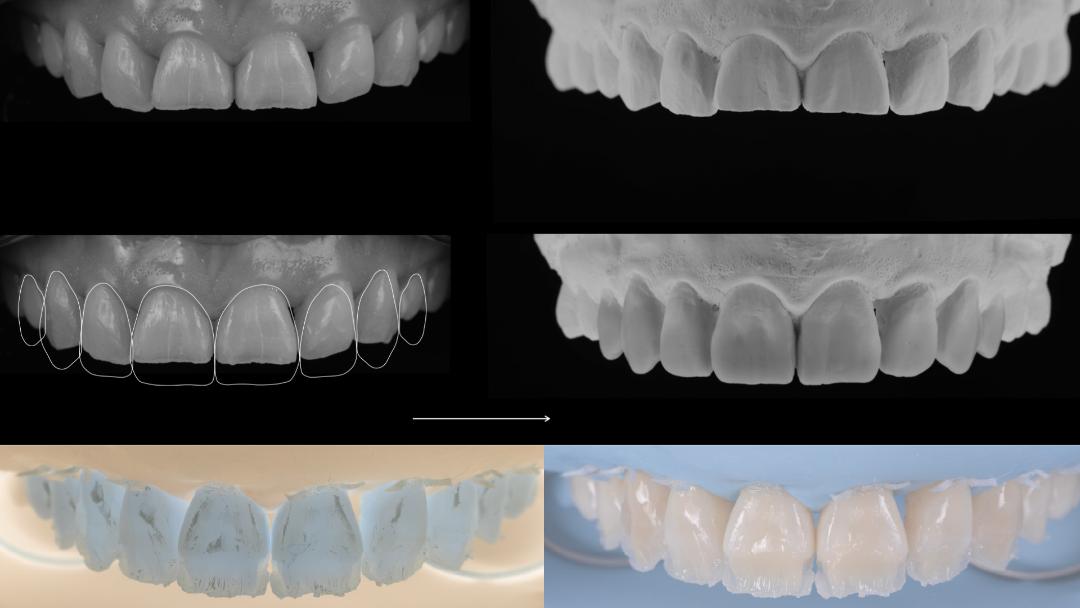

Restorative strategies in tooth-supported rehabilitations – Speaker: Giacomo Fabbri

Full day course in direct restorations, focus on morphology & shape analysis – Speaker: Tony Rotondo